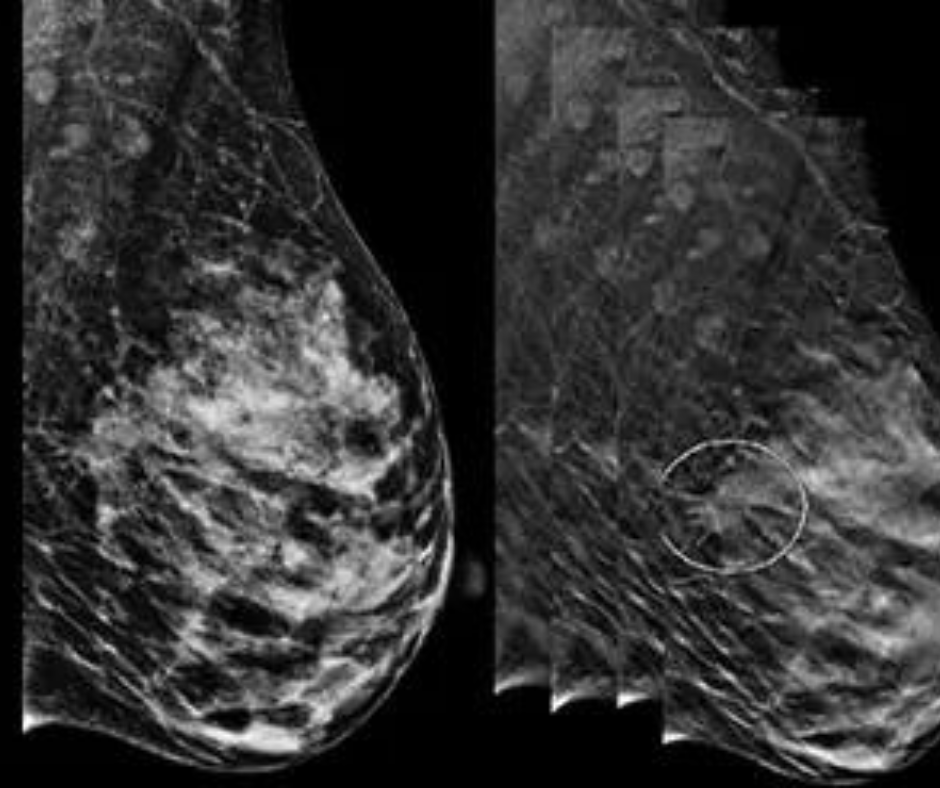

Can Contrast-Enhanced Mammography Offer a Viable Option for Pre-Op Assessment of Pathologic Nipple Involvement?